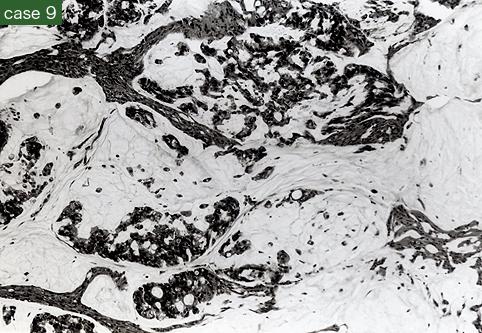

疾病(病理主体)的分类恶性上皮性肿瘤/腺癌

部位(按器官分)大肠/直肠

检查方法病理切片(微观)

肿瘤最大直径40以上